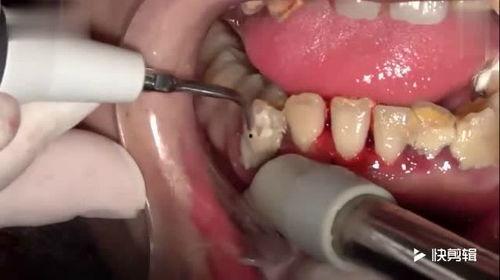

洗牙,听起来是不是有点陌生?其实,它就是通过专业的洗牙工具,清除牙齿表面的牙菌斑、牙结石,预防牙周病的一种方法。现在,越来越多的朋友开始关注口腔健康,洗牙也逐渐成为了日常生活中的一部分。

3. 洗牙操作:观看视频教程,了解洗牙的具体步骤。一般来说,先从牙齿的内外侧开始,再逐步过渡到咬合面。

4. 注意事项:洗牙时,力度要适中,避免损伤牙龈。洗牙后,要勤漱口,保持口腔卫生。